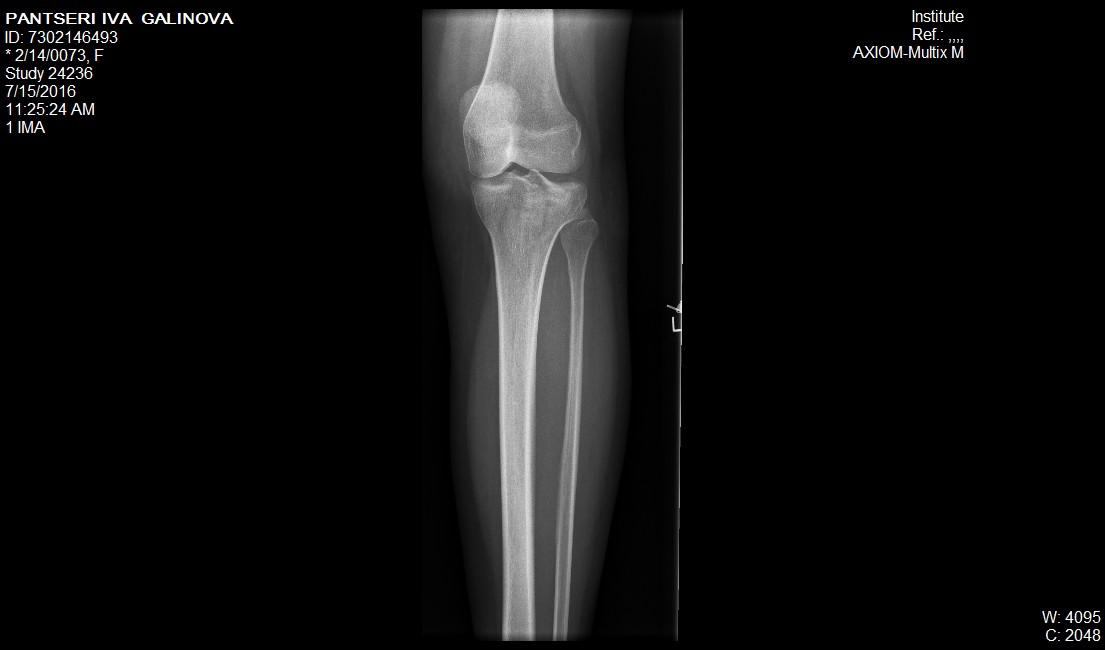

a seguito di un incidente avvenuto quattro mesi fa sono stata operata al piatto tibiale con impianto di osso sintetico e l'applicazione di osteosintesi con 6 viti. Poiche' durante l'incidente mi trovavo all'estero, l'intervento e' stato eseguito a Sofia. Adesso, dopo quattro mesi inizio a camminare ma chiedo un parere, allegando il file conuna radiografia prima dell'intervento e una fatta due giorni fa. A vostro parere era necessario un intervento simile e se si, in base all'ultima lastra vi sembra che sia tutto a posto?

15_07_16.jpg